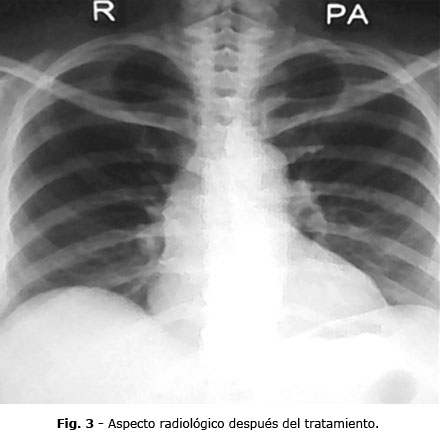

En los estudios imagenológicos se muestra que la radiografía de tórax presentaba una imagen cavitada en el ápice del pulmón derecho y ligero aumento de la trama vascular sin afectación ósea (Fig. 1). La tomografía axial computarizada (TAC) reveló la presencia de una imagen cavitada de paredes gruesas en proyección del lóbulo superior derecho hacia el segmento posterior que medía aproximadamente 39 x 32 x 53 mm. (Fig. 2).

El control radiológico (Fig. 3) mostró mejoría notable del proceso ocupativo; los exámenes de laboratorio confirmaron la mejoría de las pruebas de función renal.

A pesar de la gravedad del cuadro, la paciente no presentó lesión ósea. La osteolisis que suele observarse en estos casos es evidente en los estudios realizados como la radiografía de tórax y aún más con la TAC, como la que se le realizó a la paciente.